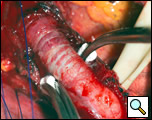

The surgical approach is a left posterolateral thoracotomy, entering the chest over the bed of the unresected 7th or 8th rib. On entering the thoracic cavity, the pulmonary ligament is divided and the lung is packed out of the way superiorly. The epiphrenic diverticulum is often found at the level of the inferior pulmonary vein. The pleura over the esophagus is divided allowing the esophagus to be gently mobilized. Penrose drains are used to encircle the esophagus superior and inferior to the diverticulum to facilitate the dissection (Figure 3). The diverticulum often arises to the right side necessitating rotation of the esophagus to clearly visualize the neck of the diverticulum. The diverticulum and its base are carefully dissected from the adjacent esophagus (Figure 4). Both vagus nerves are clearly identified and preserved during this maneuver. Once the diverticulum base is defined, a 40 Fr bougie is introduced across the gastroesophageal junction. This is performed under direct vision with the surgeon closely monitoring the safe passage of the bougie.